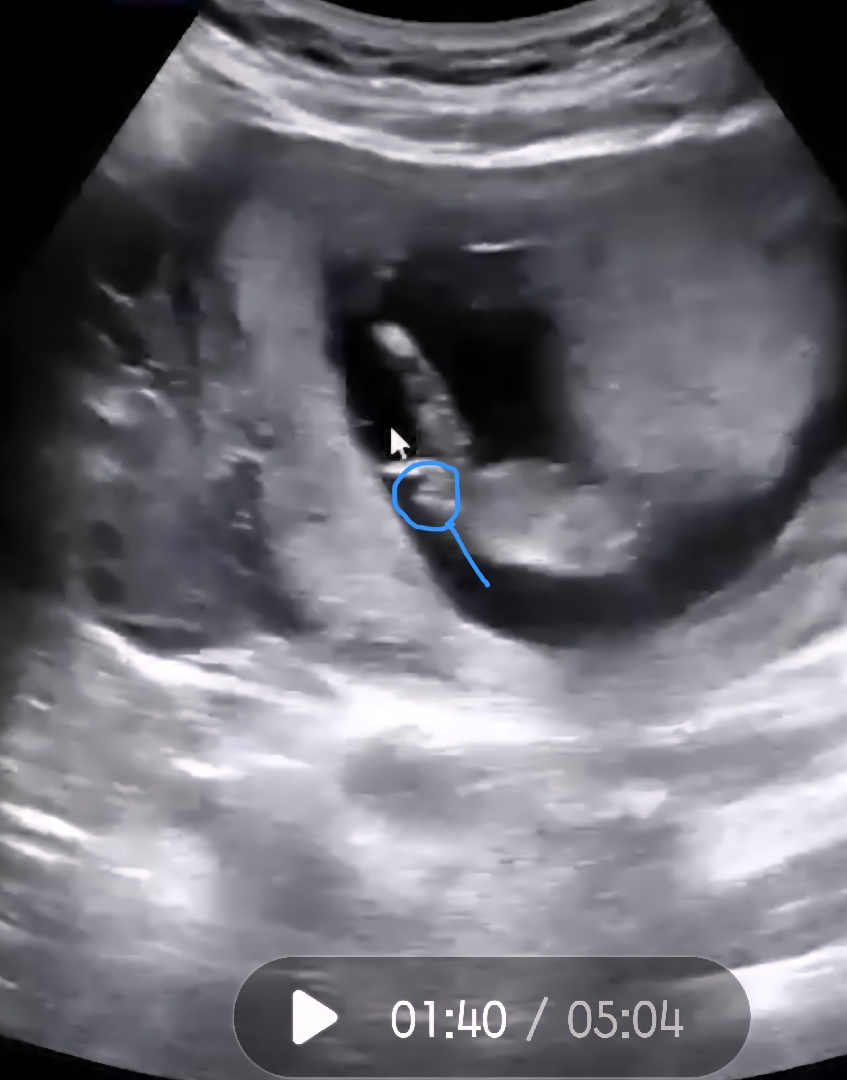

이부분은 뭘까요??

혹시 아들이여도 저렇게 되있나요?